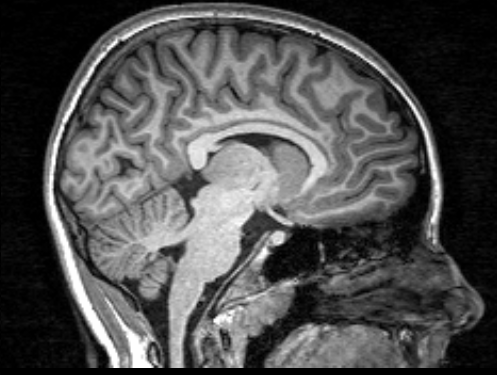

Our Department amplifies an existing collaboration with the Radiology Department (Ghent University Hospital), a major regional hospital, where we have access to a 3T high-field TIM TRIO MRI-scanner (Siemens, Erlangen). The MRI data acquisition is performed in collaboration with Prof. E. Achten, Head of the Department of Radiology at Ghent University Hospital. There is also a partnership between our research group and the Ghent Institute for Functional and Metabolic Imaging (GIfMI) on one hand, and the Multidisciplinary Research Platform (MRP) of the Institute for Neuroscience on the other hand, which provide exceptional platforms for integration of cognitive neuroscience and neuromodulation using combined resources of Ghent University and Ghent University Hospital.

Specifically, we administer five different types of specialized MRI scans to characterize the connectome, or the ‘fingerprint’ of an individual’s brain connectivity.

- Task-based functional MRI (T-fMRI) is used for non-invasive measurements of haemodynamic processes within the brain during the performance of a motor task.

- Diffusion tensor imaging (DTI) is used for anatomical investigation of the integrity of anatomical connections by providing a quantitative assessment of the brain’s white matter microstructure.

- A magnetization transfer image (MTI) is acquired to obtain a more dedicated measure of myelin integrity.

- a high-resolution T1-weighted MRI scan is administered to quantify cortical thickness and cortical surface area.

- resting state fMRI (R-fMRI) is used to evaluate specific patterns of synchronous activity that occur when a subject is not performing an explicit task.